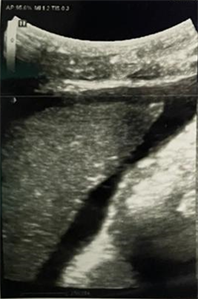

Abdominal ultrasonography showed a homogenous dysmorphic hepatomegaly with a hypertrophic caudate lobe, a splenomegaly and a mild ascites (Figure 1). Right and middle hepatic veins were obstructed. The left hepatic vein was permeable and dilated (Figure 2). We completed imaging with an abdominal computed tomodensitometry (Figure 3) with contrast enhancement. We observed the same aspect of hepatomegaly with an enlarged caudate lobe, splenomegaly and mild ascites. Moreover, the right hepatic vein was hyperechoic suggesting an obstructive thrombosis. The middle hepatic vein was also hyperechoic and partially obstructed. The left hepatic vein and the inferior vena cava were normal. These

Figure 1. Abdominal ultrasonography of November 2022 showing a peri hepatic ascites.